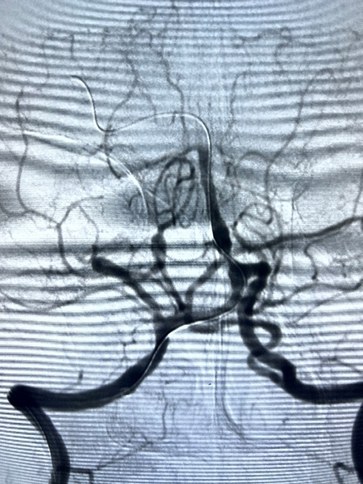

5F-115中间导管送入右侧椎动脉V3段,微导丝送入右侧大脑后动脉。

导引导管到位,导丝通过病变